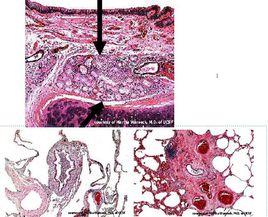

本病早期X線檢查多無異常,病程長者可見肺紋增加、粗亂,以兩下肺為著,有時可見“雙軌征”;合併感染時支氣管周圍有小片狀模糊影。